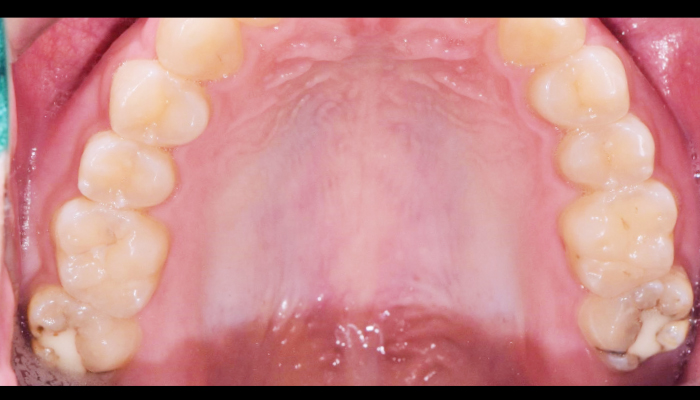

이갈이는 다양한 원인에 의해 발생되는 것으로 치아의 마모, 턱관절 통증, 두통 등을 유발합니다. 치과치료와 함께 생활습관을 교정하는 방법으로 이갈이를 줄여나갈 수 있습니다.

다양한 합병증을 동반하는 이갈이

서울바른훈치과에서는 임상검사 및 바이트스트립, 필요시 치과에서 제작한 이갈이 검사장치를 이용하여 이갈이를 정확하게 진단하고 이와 동반된 치아시림, 턱관절장애, 안면부 근육통, 두통, 사각턱까지 총체적으로 치료가 가능합니다.